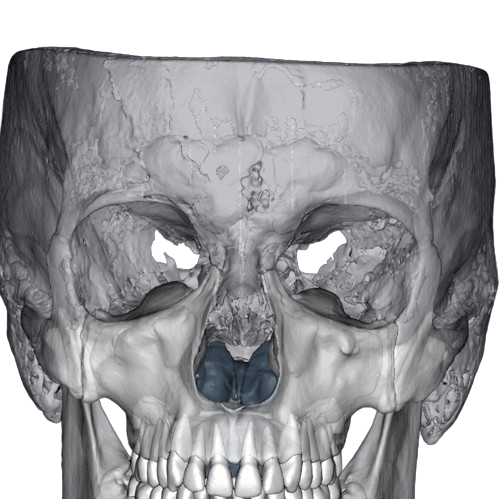

Об’єм: 20×17 см

1400 ₴

Допомагає визначити особливості будови черепа в цілому і підходить для планування хірургічних і ортогнатичних операцій.

Записатися Детальніше

Об’єм: 16×10 см

1200₴

Допомагає оцінити стан обох щелеп, придаткових пазух і височно-нижньощелепних суглобів.

Записатися Детальніше